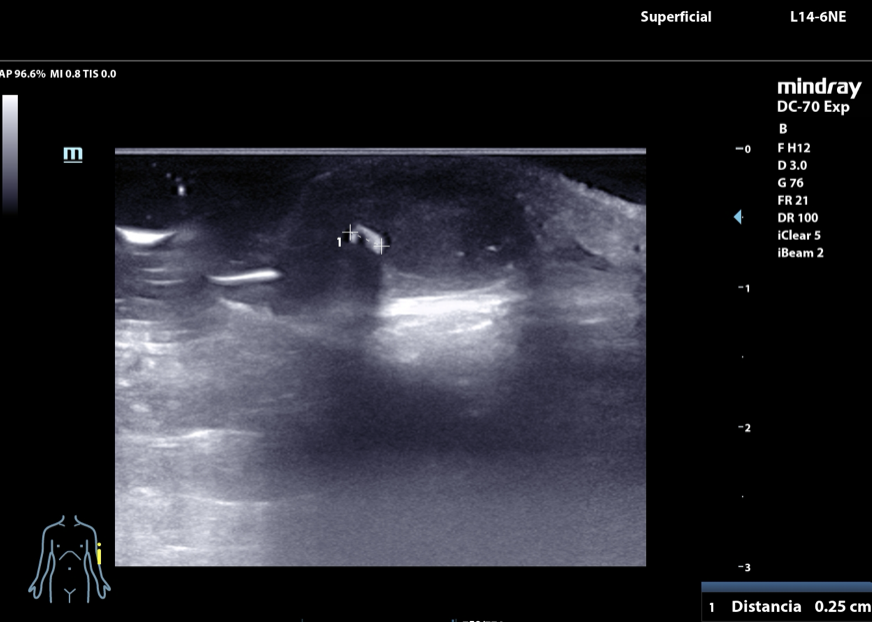

• Ecografía músculoesquelética en agosto de 2024 en la que se identifica un cuerpo extraño de 43 mm de longitud que deja sombra posterior y que se localiza a nivel del vientre del músculo braquioradial.